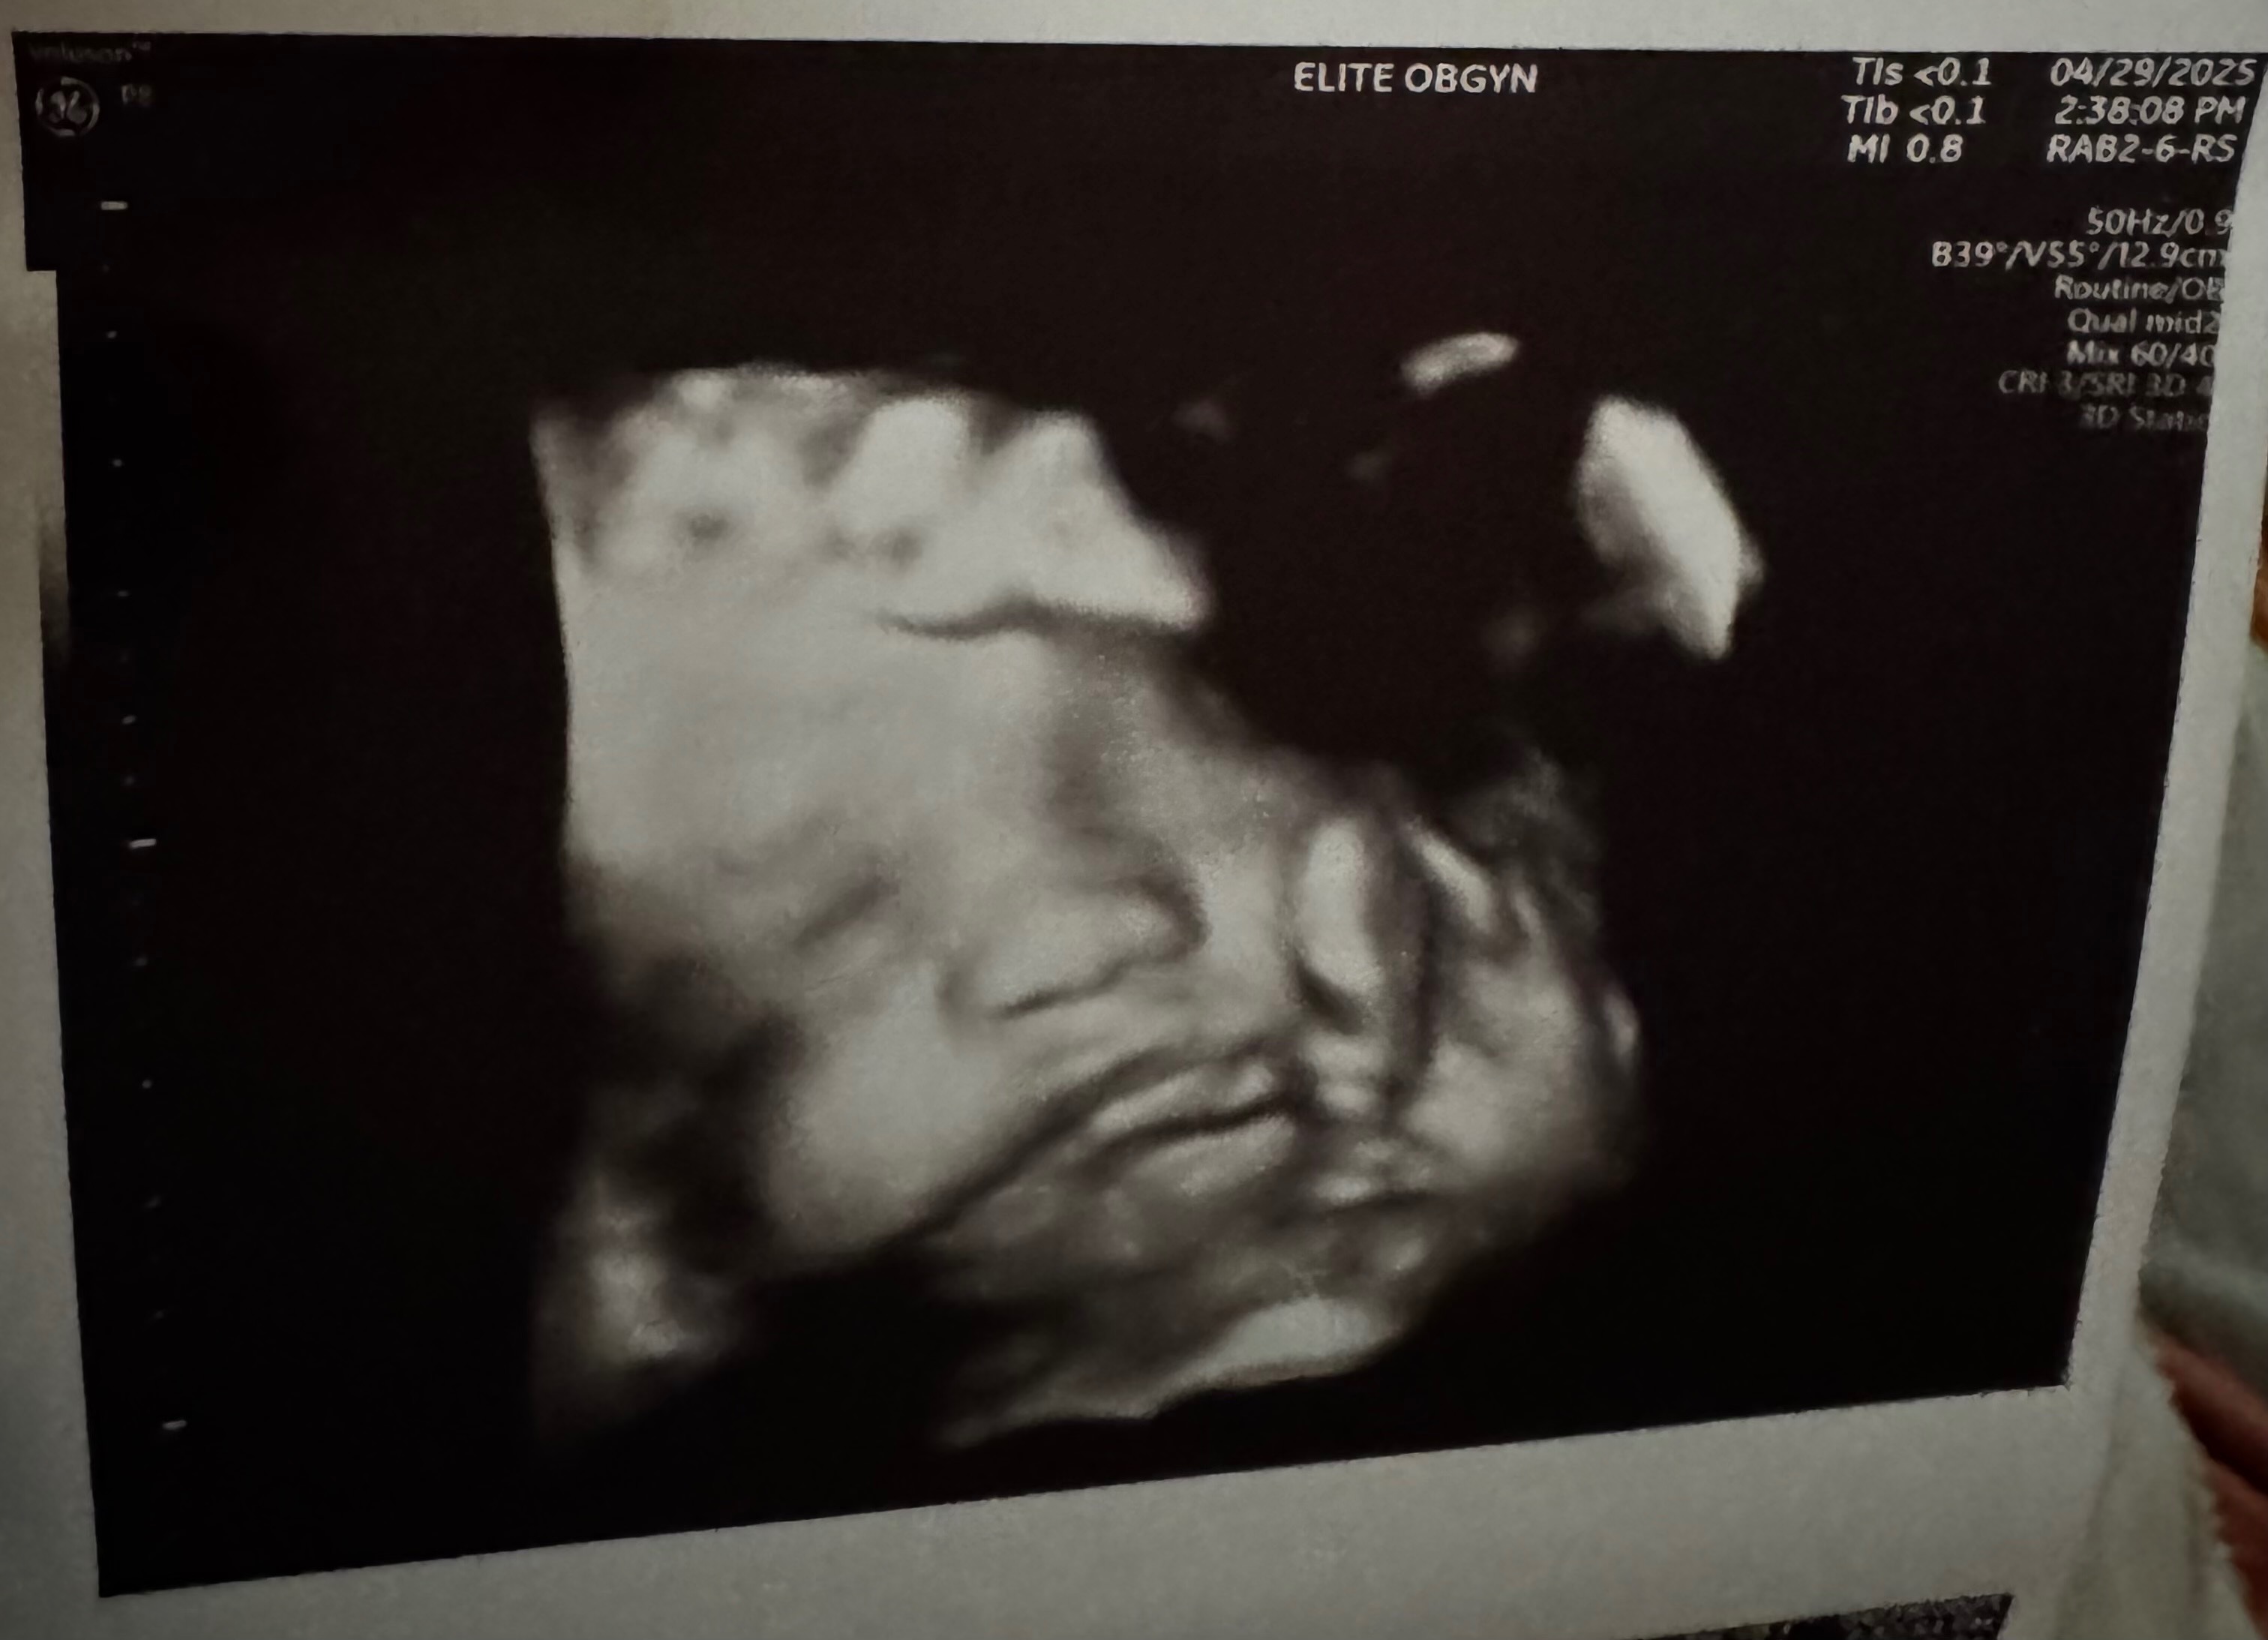

I need everyone to share my story and support my go fund me . On June 9th I went in for a ultra sound at 37 weeks. By June 13th I was being rushed to the hospital. Because my baby was no longer moving. His death was caused due to the umbilical cord wrapped around his neck. A 3d ultra sound was never performed. I know my baby would still be here if the doctor had. Done the proper procedures.